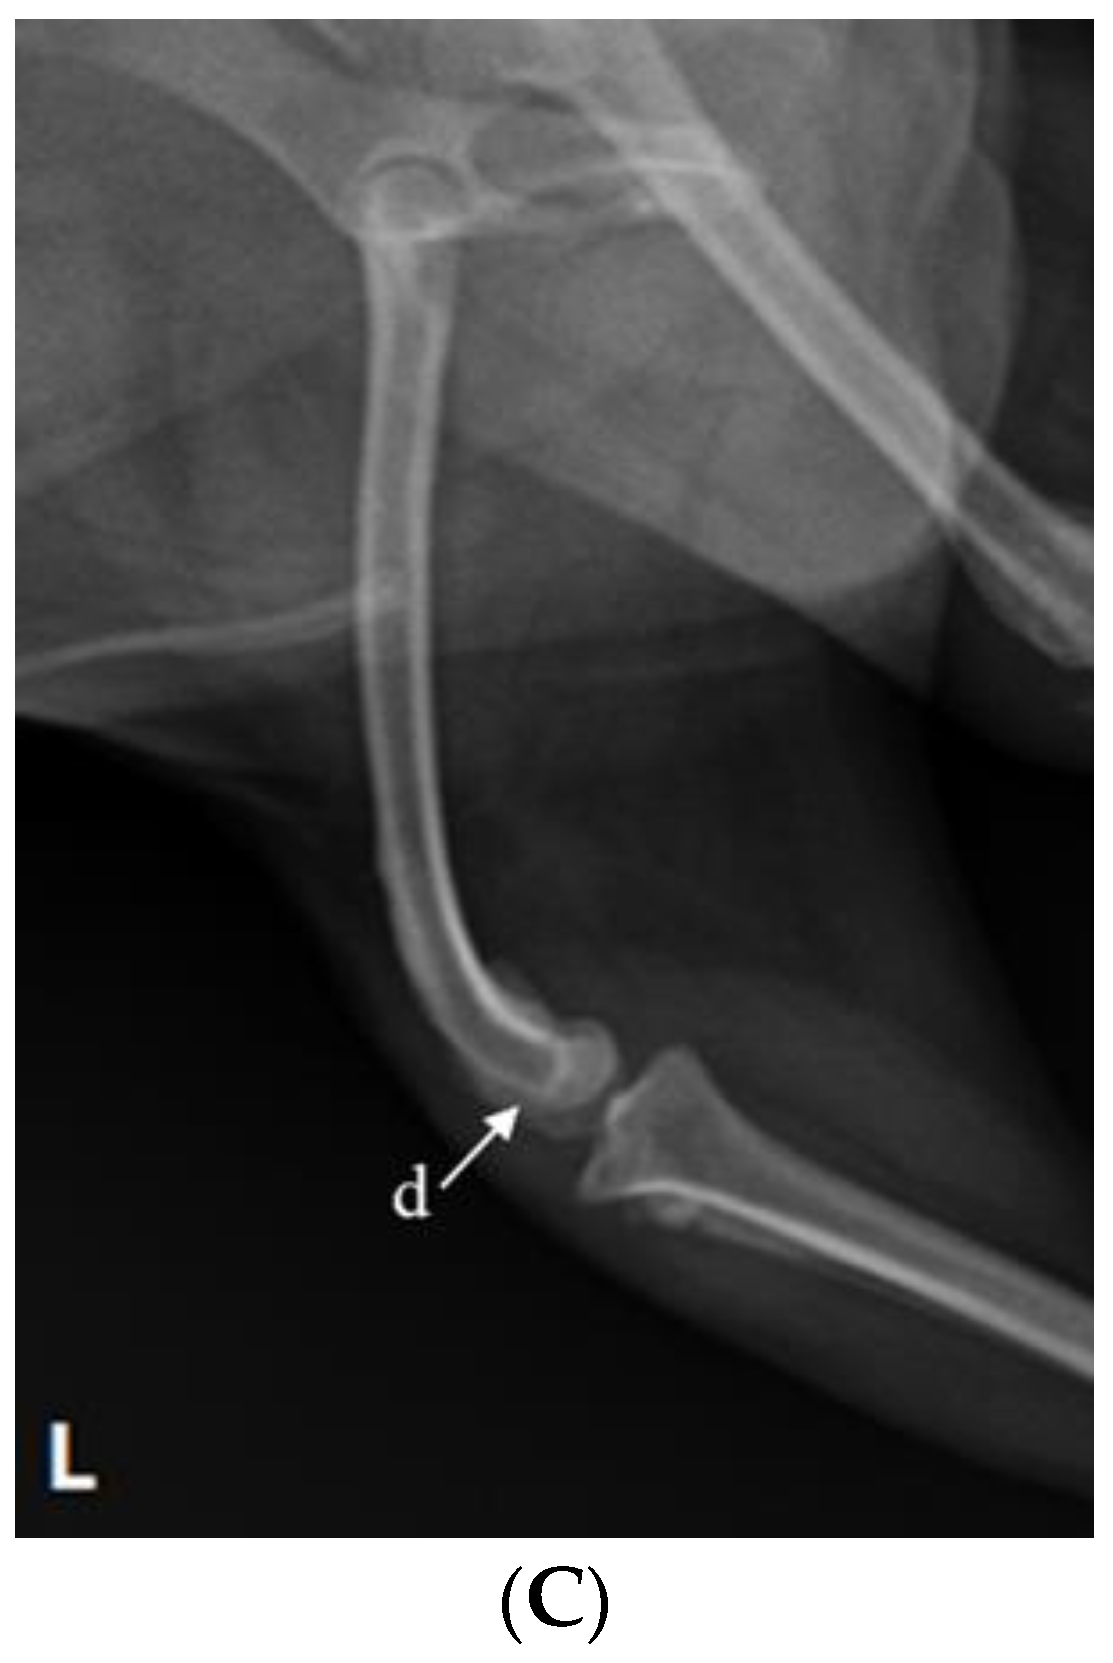

After incising the articular capsule, the femur and tibia were exposed by rotating the joint capsule 180° laterally using Allis tissue forceps (23 cm, KASCO, Islamabad, Pakistan) (Figure 3B). A rupture of the cranial cruciate ligament was confirmed in the process of exposing the stifle joint. The tissue attached around the stifle joint was partially removed, and fibrous adhesive tissue that interfered with flexural movement was separated and removed (Figure 3C). The distal end of the femur and the proximal end of the tibia were flattened with a bone file and rasp (Bone rasp and File, Professional, Sialkot, Pakistan) and a rongeur (Single bone rongeur, 12 cm, Mabson industry, Sialkot, Pakistan), allowing the plate and the joint surface to be attached. Cancellous bone was extracted during the process of flattening the joint surface. It was stored in an empty syringe to avoid contamination and served as an autologous graft for improving bone union. In order to fix the stifle joint at an angle of 120–130°, using a K-wire (1.4 mm × 229 mm, General Vet Products, Fairy Meadow, Australia), a guide pin was inserted through the medial surface of the tibia in an upward direction of 45° with respect to the medial condyle of the femur. In the same way, the stifle joint was fixed using two guide pins positioned in an ‘x’ shape (Figure 4). Cancellous bone tissue was transplanted into the stifle joint cavity. The angle and location of the plate (ID = 2.0 mm and length = 8.5 cm, Orthotech, Daegu, Republic of Korea) for SJA were confirmed using a C-arm machine (7700 Compact C-Arm, Hi Tech International Group Inc., Deerfield Beach, FL, USA) and fixed on the front of the femur and tibia. The screws used for fixing the plate were 1.5 mm and 2.0 mm in size (Veterinary Instrumentation, Doiff, Suncheon, Republic of Korea) and inserted from the proximal part of the femur to the distal part and, alternatively, from the distal part of the tibia to the proximal part (Figure 4A,B).

Figure 4.

Radiograph images depicting the stifle joint arthrodesis performed on the right hind limbs and the medial patellar luxation correction of the left hind leg. (A) Craniocaudal radiographic view of both stifle joints. (B) Mediolateral radiographic view of stifle joints following SJA. (C) Postoperative mediolateral view of MPL in the left hindlimb.

2.4. Reconstruction of MPL

After performing SJA of the right hind limb, MPL correction of the left hind limb was performed. The approach was carried out by making a vertical incision of about 10 cm in the craniolateral parts around the stifle joint. After the fascia and articular capsule were incised to expose the trochlea of the femur, tracheoplasty was performed in a wedge shape to secure the depth of the trochlea. Then, the wedge-shaped articular cartilage was inserted into the femoral trochlea. Subsequently, a tibial tuberosity that had moved toward the inside was cut using a bone saw and moved laterally to fit the patella into the trochlear groove using a K-wire (Figure 4A,C). Stability was further enhanced using the figure-of-eight-tension-band-wiring technique. Before suturing, the distal tibia was rotated internally and externally 2–3 times to confirm that the patella (Figure 4A,C) remained stable in the newly formed trochlear groove. Subsequently, routine closure was performed in the following order: joint capsule, muscle, subcutaneous tissue, and skin.